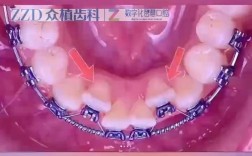

正畸治疗的核心是让牙齿在牙槽骨内缓慢移动至理想位置,而移动的前提是“空间”,当存在牙齿拥挤、牙量与骨量不匹配、咬合异常等问题时,就需要通过拔牙、磨牙或扩展牙弓等方式创造空间,磨牙(去釉)是一种“微创减数”手段,通过少量磨除牙齿邻面的牙釉质,无需拔牙即可获得间隙,尤其适用于特定情况的轻中度拥挤。

- 解决轻度牙列拥挤:当牙齿拥挤量较小(通常每颗牙磨除0.2-0.5mm,10颗牙可提供2-5mm空间)时,通过磨除邻面牙釉质,可避免拔牙,同时排齐牙齿。

当拥挤量≤4mm,且患者面部形态、咬合功能良好时,磨牙可替代拔牙,上颌前牙拥挤2-3mm,通过磨除10颗前牙邻面各0.2-0.3mm,即可获得足够排齐空间。